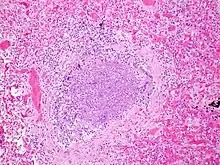

.jpg.webp)

The term usually refers to acute viral bronchiolitis, a common disease in infancy. This is most commonly caused by respiratory syncytial virus[13] (RSV, also known as human pneumovirus). Other agents that cause this illness include human metapneumovirus, influenza, parainfluenza, coronavirus, adenovirus, rhinovirus and mycoplasma.[14][15]